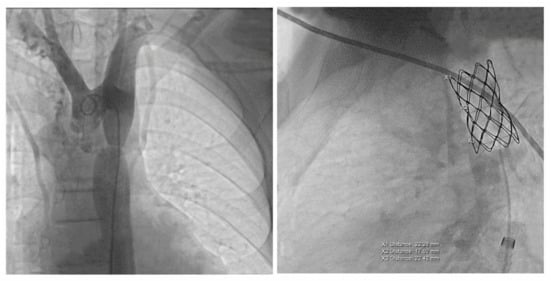

2.3. Therapeutic Approach, Postprocedural Evolution, Cardiologic Follow Up